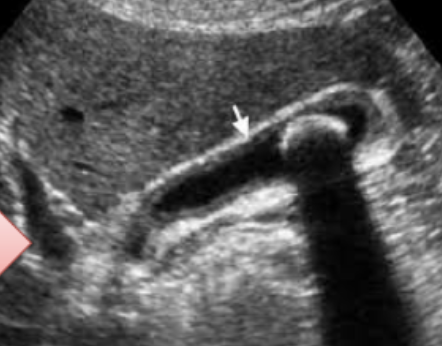

1- What is your diagnosis?

Chronic calcular cholecystitis.

2- Give 4 complications? -

- Pancreatitis. -

- Obstructive jaundice. -

- Gall bladder cancer. -

- Cholangitis

Acute Calcular Cholecystitis

U/S from patient with recurrent upper abdominal pain.

Diagnosis -

calculous cholecystitis

Four common complications

- peritonitis

- perforation

- choledocholithiasis

Gallbladder stone (calcular cholecystitis)

Complication:

- cholangitis,

- choledocholithiasis,

- pancreatitis,

- gallbladder perforation

Imaging technique:

- ultrasound

An ultrasound image from a patient with recurrent upper abdominal pain.

Q1: What is your diagnosis?

- Cholecystitis

Q2: Name FOUR common complications of this disease.

- Peritonitis,

- Perforation,